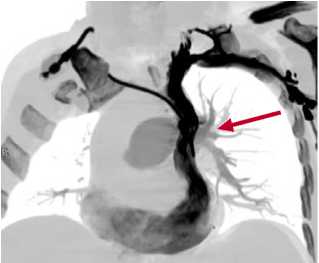

По данным КТ флебографии верхняя полая вена расположена по левому краю средостения, впадает в коронарный синус, далее в области основания сердца в правое предсердие (Рис. 4).

Рис. 4. КТ флебограмма. Стрелочкой показана персистирующая левая верхняя полая вена.